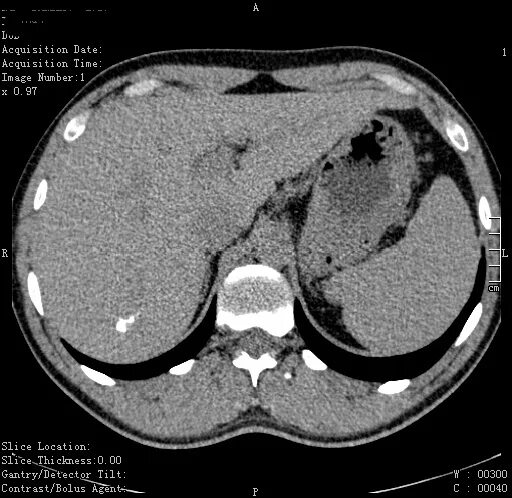

Кт тканей